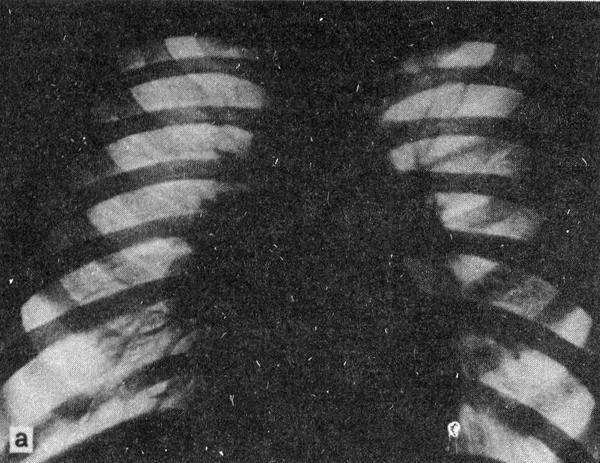

Саркоидоз внутригрудных лимфатических узлов

Важным признаком являются кальцинации, которые нередко склоняют толкование процесса в сторону туберкулеза. В настоящее время общепризнано, что внутригрудные лимфатические узлы при саркоидозе в 29 … 30 % случаев могут иметь включения солей кальция. Саркоидозу свойственны множественные кальцинации, отстоящие от стенок бронхов и трахеи. Их наблюдают обычно у больных с длительным течением болезни или как результат клинического излечения.